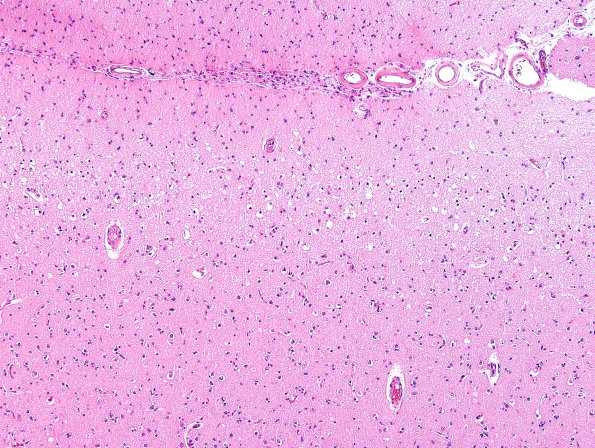

Washington University Experience | METABOLIC | Hypoglycemia | 2C3 Hypoglycemic Coma (Case 2) N1 H&E 1

The first indication of cortical injury in the area of 2C1 marked with an arrow is the development of vacuolation in the superficial cortical layers; however, further inspection suggests ongoing neuronal necrosis in deeper layers as well. (H&E)